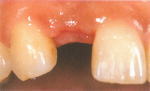

歯を1本だけ失った場合

ブリッジによる治療だと、ブリッジを支えるために健康な歯を2本削らなければなりません。

一方、インプラント治療では、インプラントを1本入れるだけで他の歯に悪影響を与えません。また、見た目が美しく、あたかも自分の天然歯のように自然に感じられます。治療後は、顎骨の萎縮の心配も無く、本来の骨量を維持できます。